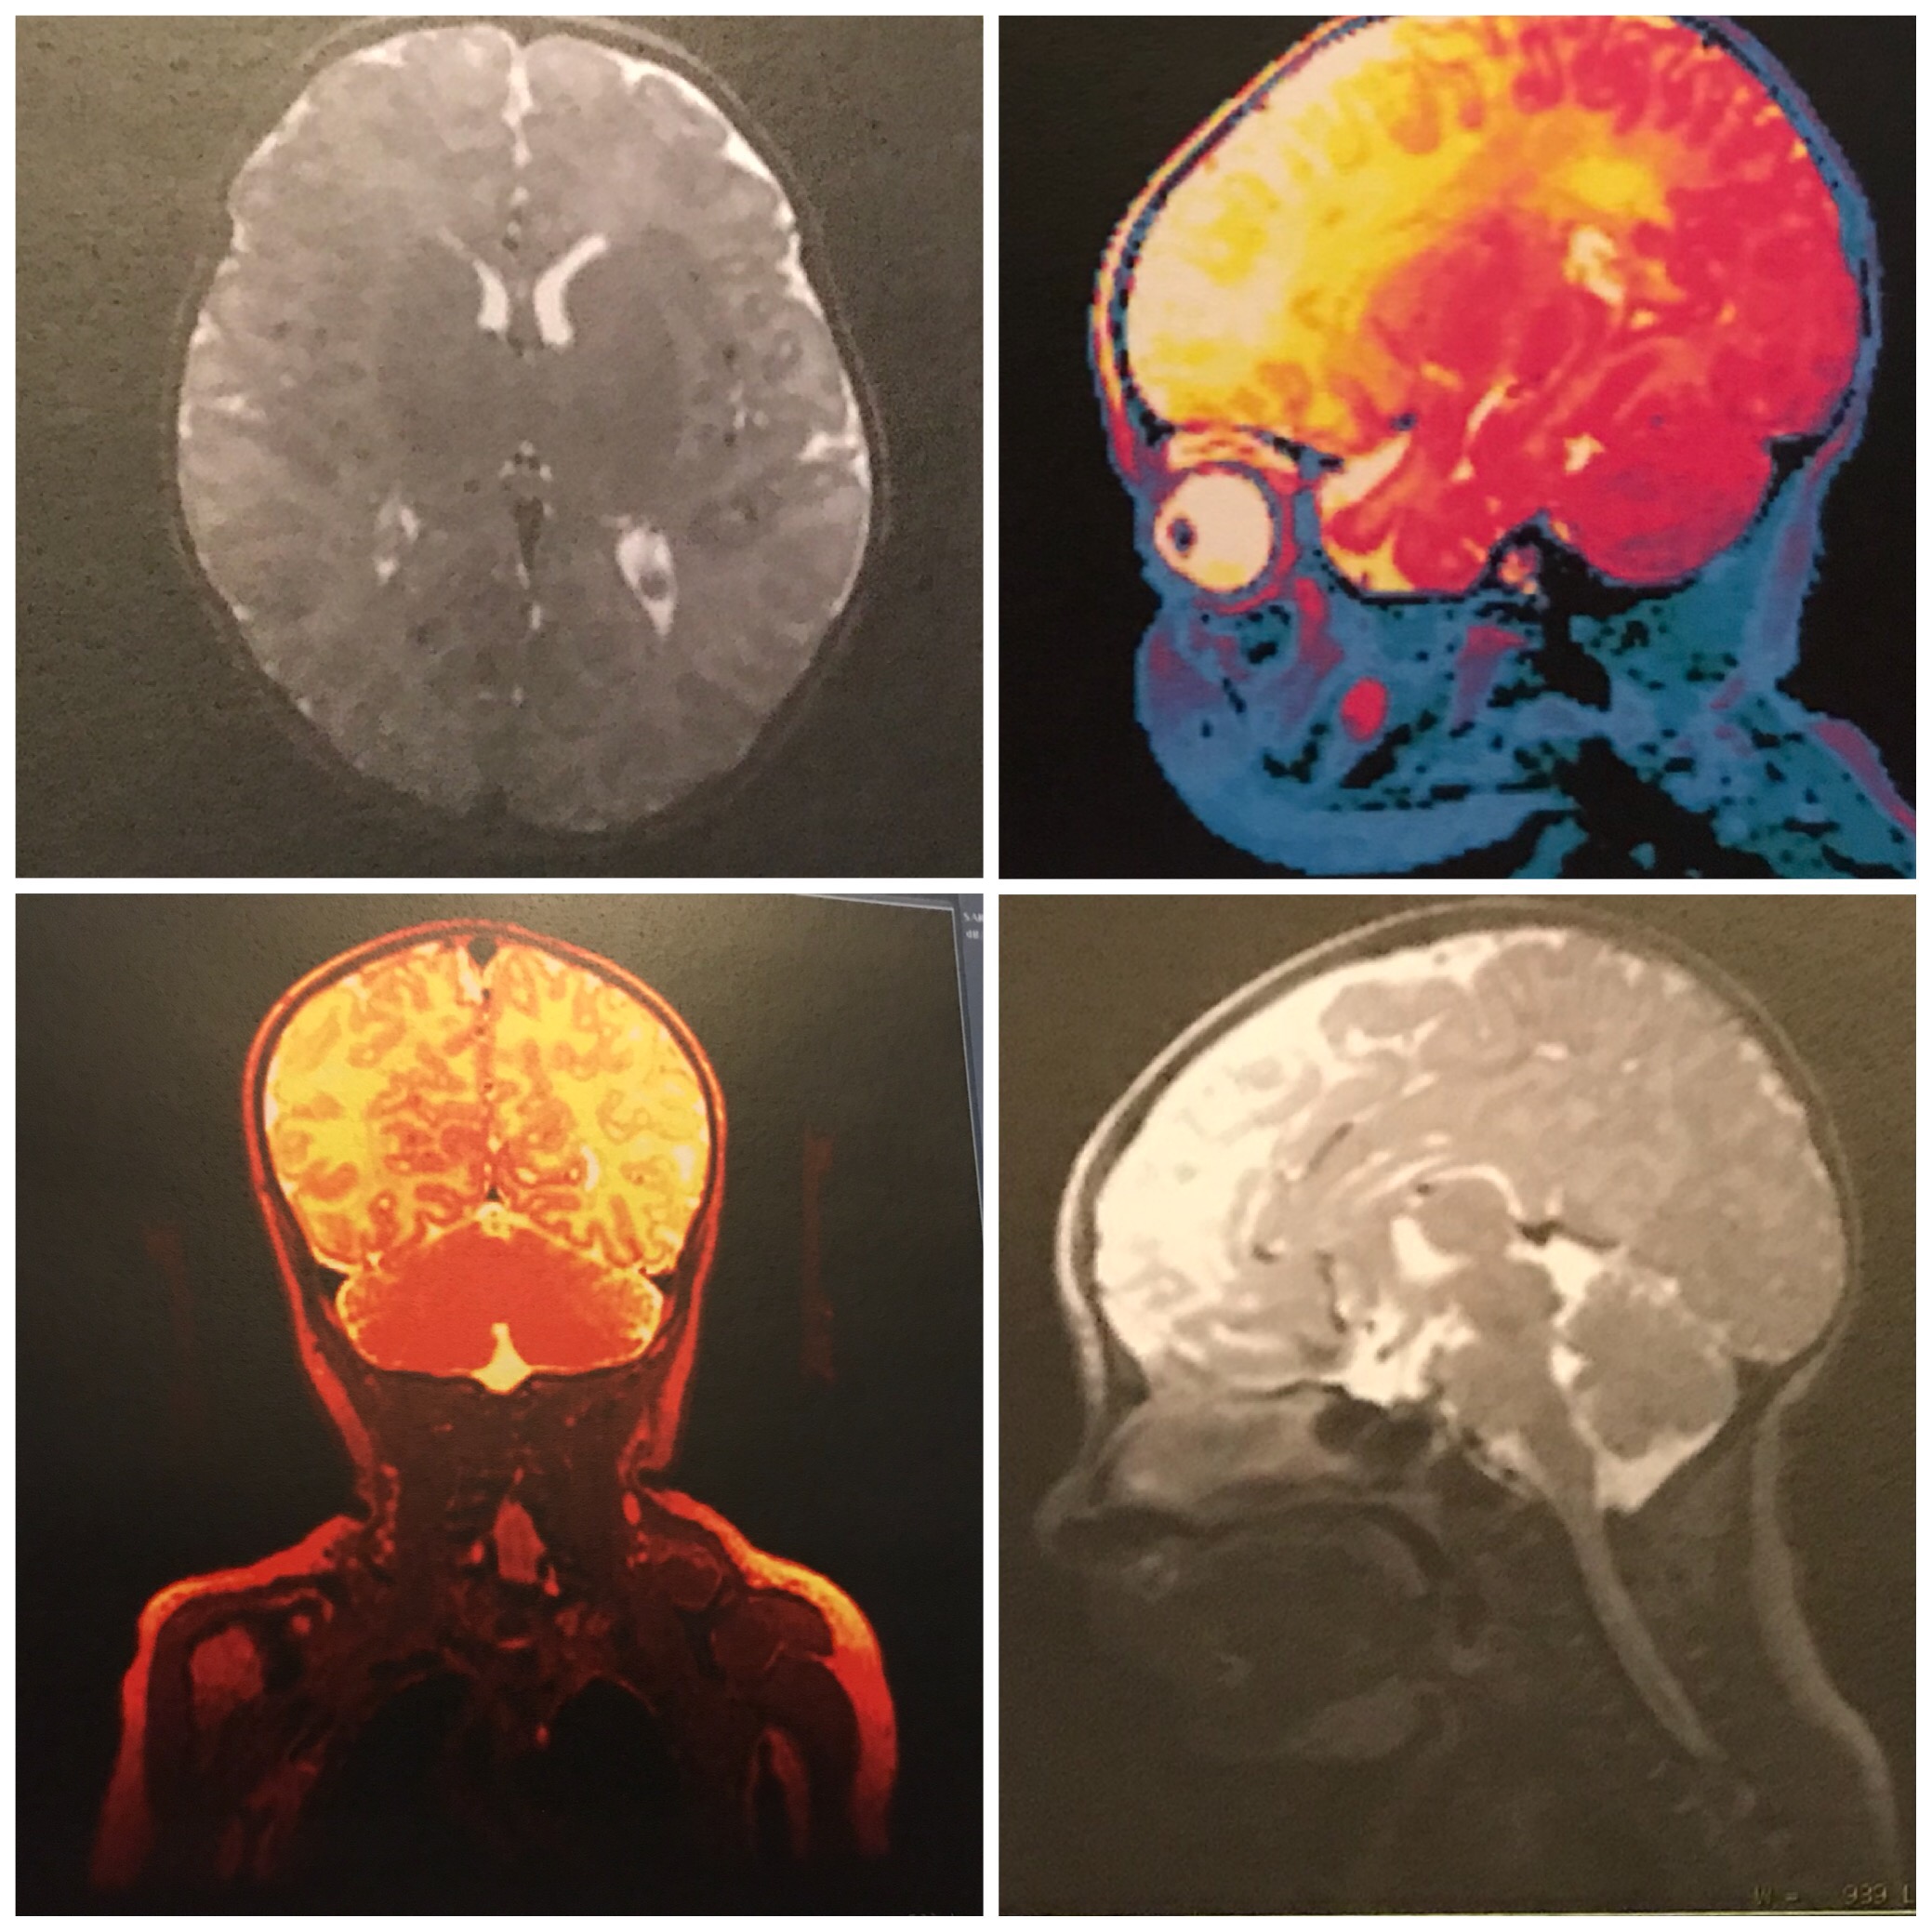

I was given copies of his scans, in both color and black and white. It’s amazing that you can see brain, eyes, lungs and even teeth that will come in later in them.